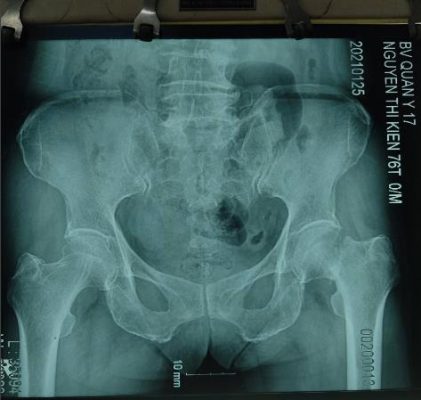

Gãy cổ xương đùi di lệch Thay khớp háng toàn phần điều trị gãy cổ xương đùi di lệch

- Chấn thương khớp háng: gãy cổ xương đùi di lệch ở bệnh nhân cao tuổi; gãy nhiều mảnh chỏm xương đùi; gãy liên mấu chuyển mất vững ở bệnh nhân cao tuổi, loãng xương nặng mà trước đó chức năng khớp còn tốt.